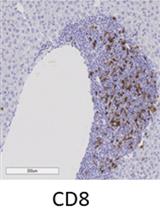

Immunohistochemistry of Immune Cells and Cells Bound to in vivo Administered Antibodies in Liver, Lung, Pancreas, and Colon of B6/lpr Mice

Employing a novel mouse model of immune related adverse events (irAEs) induced by combination of anti-PD1 and anti-CTLA-4 antibodies, we visualized immune infiltration into the liver, lung, pancreas, and colon. Here, we describe the avidin-biotin conjugate (ABC) method used to stain T cells (CD4 and CD8), B cells (CD19), macrophages (F4/80), and cells bound by the in vivo administered rat anti-mouse antibodies for chromogenic immunohistochemistry (IHC). Using a biotinylated goat anti-rat antibody, we detected the localization of cells bound to the in vivo antibodies for PD-1 and CTLA-4. IHC has advantages over other techniques, namely antibody availability, resistance to photobleaching, and greater sensitivity. Additionally, detection and localization of in vivo antibodies can be used in mice models to infer their therapeutic efficacy, stability, and function.Graphical abstract: